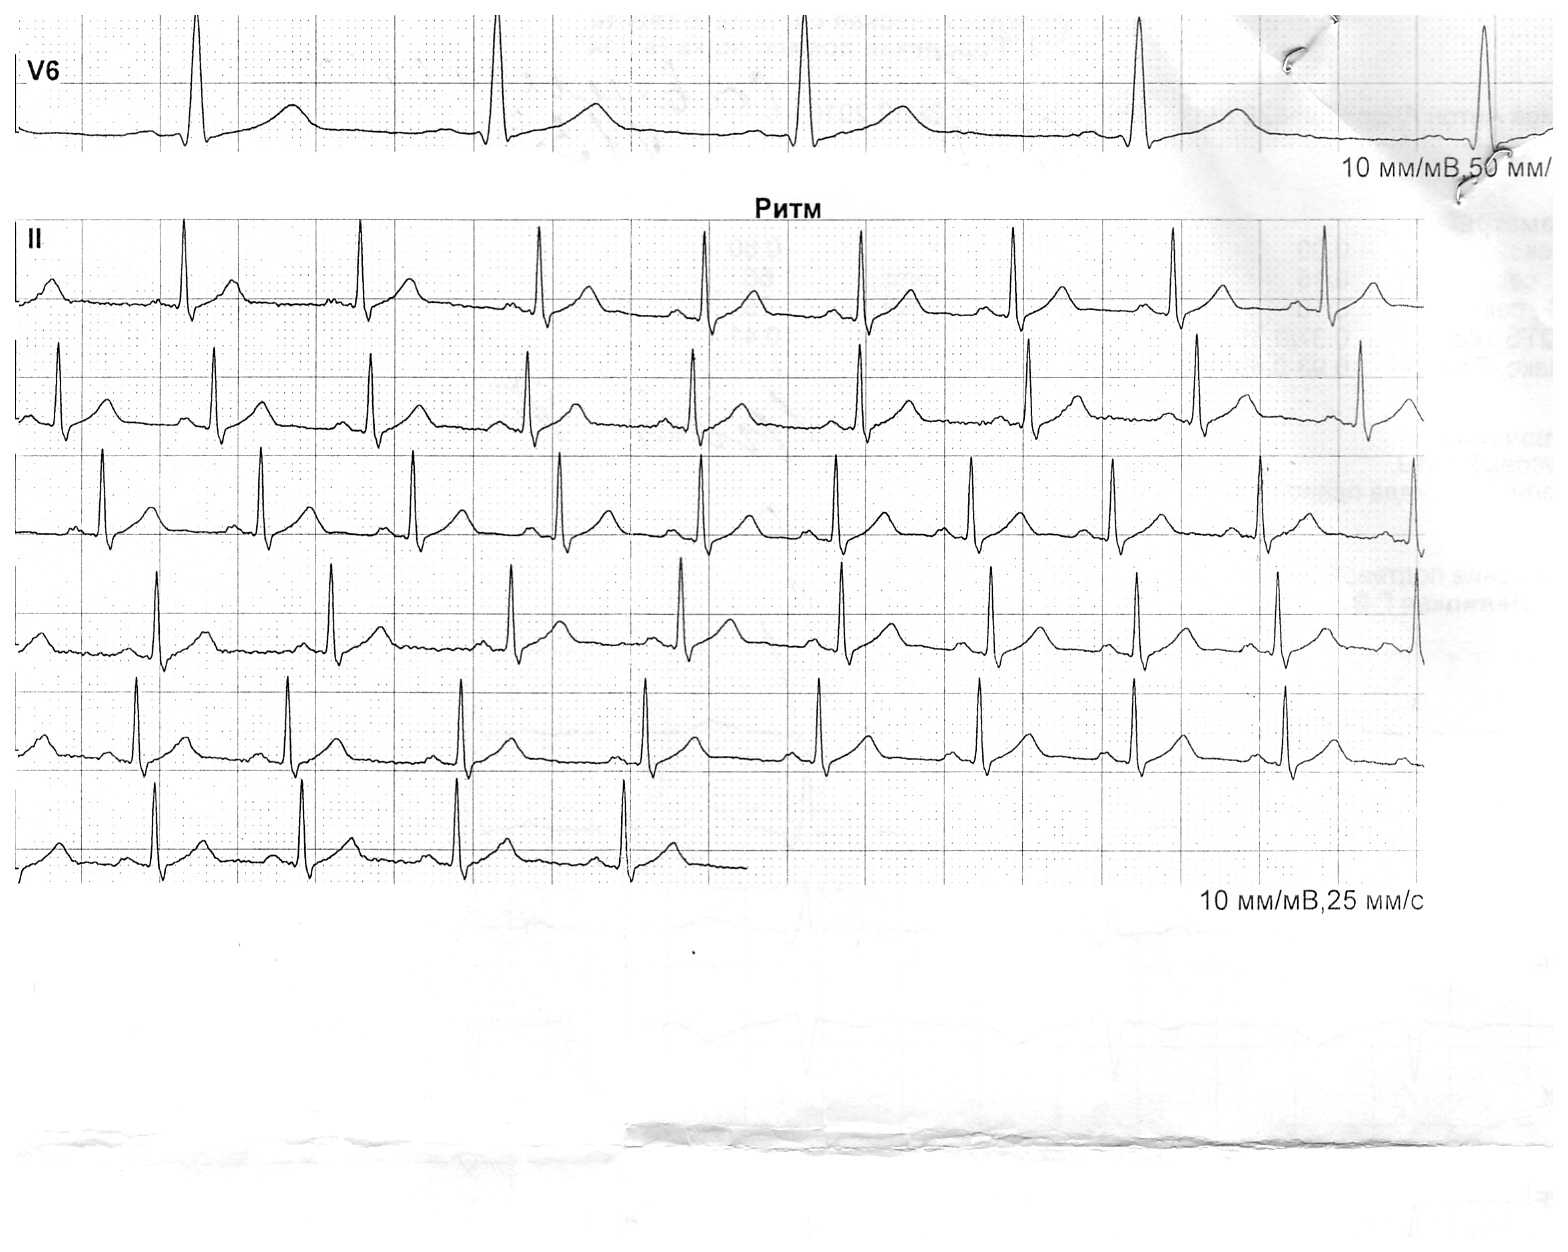

Доктор, здравствуйте! У меня тут такая проблема. Недавно с удивлением заметил, что пульс в покое очень высок (80-90). На кардио вообще запросто взлетает до 160, при этом никак негативно не ощущается, скорее ощущается даже недостаток нагрузки. (Кардио делаю редко, даже очень). Вес 94, рост 185, возраст 29. Давление обычно в норме, 110-120 на 70. Есть полугодичное узи и экг, могу скинуть если надо.

В чем дело? Что то мне это не очень нравиться. Несколько лет назад у меня была явная склонность к брадикардии, в покое чсс было точно не больше 50.

Вот такие есть:

Ветка спортивного кардиолога - Бодибилдинг форум AnabolicShops Ветка спортивного кардиолога - Бодибилдинг форум AnabolicShops Ветка спортивного кардиолога - Бодибилдинг форум AnabolicShops

Тромбо асс, милдронат 1г, редко - аспаркам. Недавно начался курс тест (500) болд(800) оксандролон(30). В прошлый раз я повышенного сердцебиения не наблюдал... Да и я начал замечать это явление еще до курса.

Самочувствие хорошее, вот только цифры пульса сильно настораживают... Если не следить, то запросто уходит до 160-180, и я даже этого не замечаю.